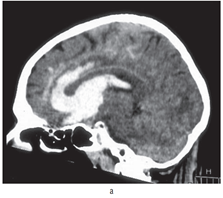

Внутримозговые гематомы, помимо этиологии, подразделяют по локализации и объему. В подавляющем большинстве случаев (до 90%) гематомы локализуются в супратенториальных отделах мозга. Различают лобарные, латеральные, медиальные и смешанные внутримозговые гематомы (рис. 12.1).

• Лобарными называют кровоизлияния, при которых кровь не выходит за пределы коры и белого вещества соответствующей доли или долей головного мозга.

• Кровоизлияния в подкорковые ядра (кнаружи от внутренней капсулы) принято обозначать как латеральный инсульт, а кровоизлияния в таламус — как медиальный инсульт (кнутри от внутренней капсулы).

• На практике чаще всего встречают смешанные внутримозговые гематомы, когда кровь распространяется в пределах нескольких анатомических структур.

Рис. 12.1. Внутримозговые гематомы разных локализации и объема (компьютерная томограмма): а — небольшая смешанная внутримозговая гематома правого зрительного бугра, внутренней капсулы и подкорковых ядер; незначительная компрессия и смещение задних отделов III желудочка влево; б — внутримозговая гематома правой теменной доли, средних размеров; умеренное смещение срединных структур влево; в — большая смешанная внутримозговая гематома передних отделов левого полушария с прорывом в правый боковой желудочек; выражены компрессия и дислокация мозга вправо

Гематомы задней черепной ямки составляют около 10% всех внутримозговых гематом. Чаще всего они расположены в мозжечке, реже — в стволе головного мозга, где их излюбленной локализацией бывает мост (рис. 12.2).

Кровоизлияния в медиальные отделы больших полушарий мозга, а также гематомы задней черепной ямки приблизительно в 30% случаев сопровождаются прорывом крови в желудочковую систему.

Объем внутримозговых гематом при геморрагическом инсульте может варьировать в очень широких пределах — от нескольких миллилитров до 100 мл и более (см. рис. 12.1, 12.2). Существуют различные способы определения объема гематомы. Наиболее простой из них — способ расчета объема по данным КТ с использованием следующей формулы: максимальная высота × максимальная длина × максимальная ширина : 2. Распределение гематом по объему весьма условно. Принято деление на небольшие (до 20–30 мл), средние (до 50–60 мл) и большие (>50–60 мл) гематомы. Небольшие, средние и большие гематомы встречаются приблизительно с одинаковой частотой.